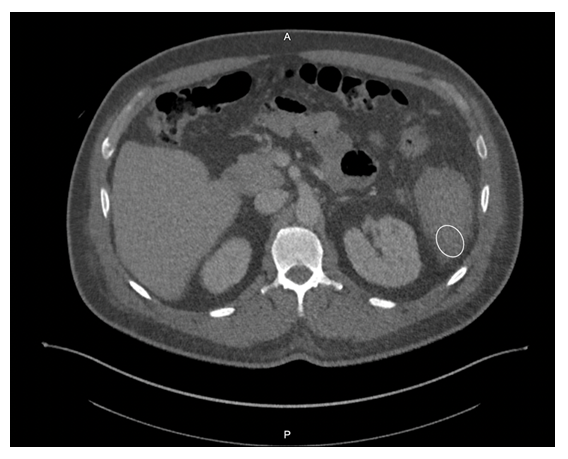

Given his symptomology, further evaluation and management were undertaken. CBC showed a drop in hemoglobin from 10.3 g/dL to 8.5 g/dL, and imaging revealed splenomegaly with a caudally located subcapsular hematoma (Figure 1). Small hemoperitoneum on the pelvis with small non-loculated fluid along the bilateral paracolic gutters was also observed. The patient received two units of packed red blood cells to stabilize his hemoglobin levels.

Figure 1Computer Tomography scan of the abdomen reveals a caudally located subcapsular hematoma (white circle).